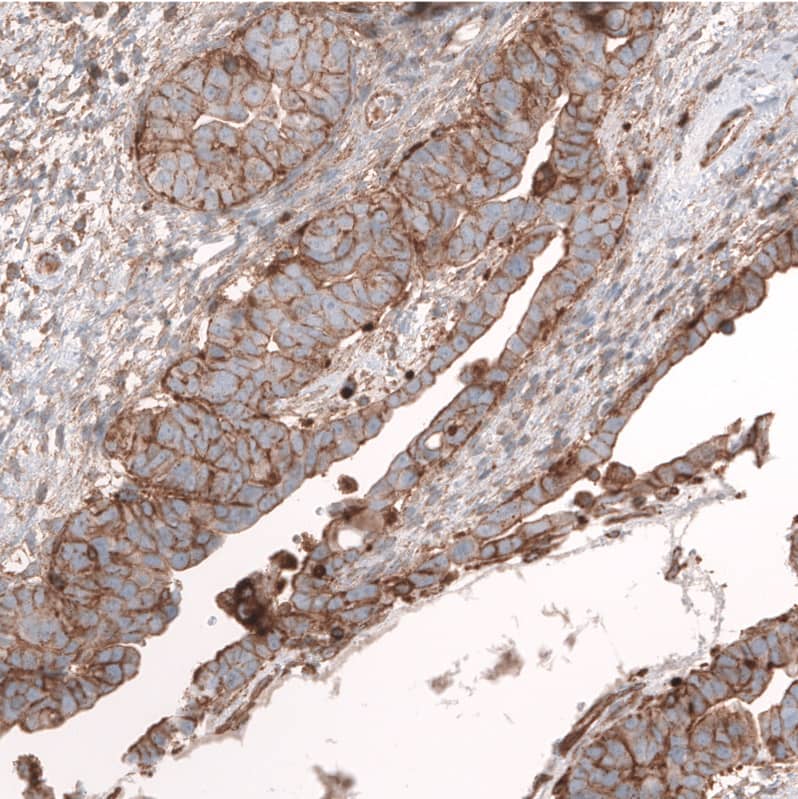

Staining of human ovarian cancer (papillary carcinoma) shows strong membranous positivity in tumor cells.